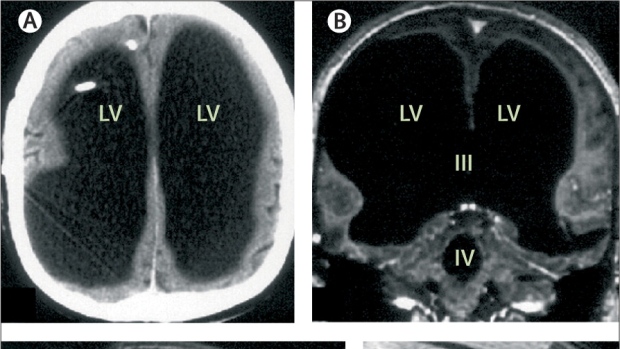

The man who lives a functional life with most of his brain filled with water challenges what we know about the brain.